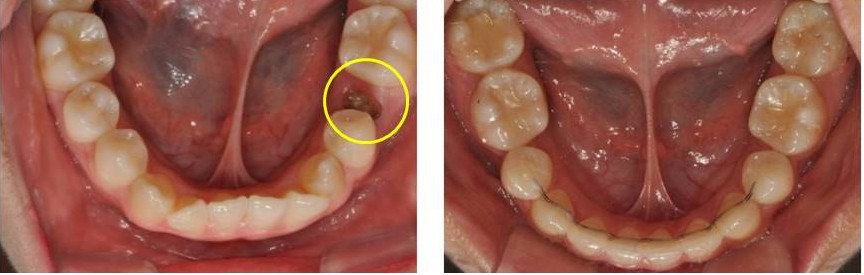

충치로 두번째 작은 어금니가 부러진 환자입니다. 덧니를 배열하기 위해 살릴 수 없는 작은 어금니의 뿌리를 제거하고 해당 공간을 이용하여 치아를 배열 하였습니다. 임플란트 할 필요 없이 교정 치료를 통해 덧니도 배열하면서 공간이 폐쇄된 경우입니다.